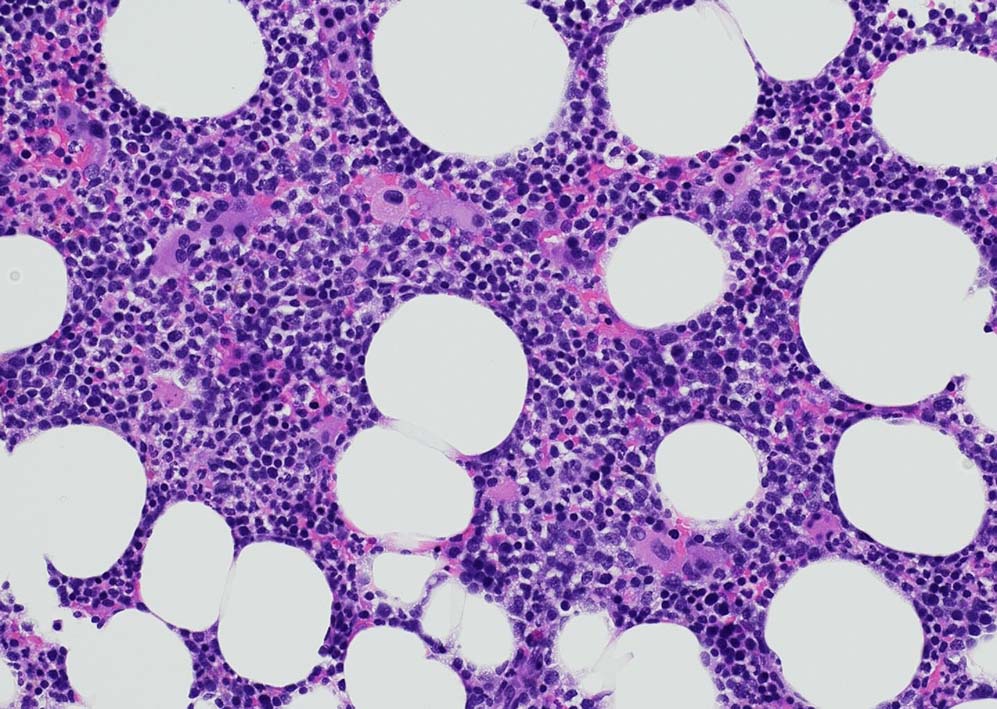

80歳代男性. 徐脈で治療中, 末梢血で血球異形成を指摘される. Hb8.8g/dl, RBC 402x104/μl, MCV 76, WBC 2500/μl, Plt. 3.9x104

Megakaryopoiesis; Mgkは増加している. 多数の分離円形核巨核球が出現している. microMgkが増加している.

Myelogram: M/E = 1.77,Blast-M 5.2%, promyelo 7.0%, Myelo 11.4%, Meta 10.0%, Stab 5.4%, Seg 18.8%, Eo mature 0.6%, Ba mature 0.6% Mo 3.0%, Lympho 4.4%, Plasma 0.2 骨髄WT1 R 1.1x104